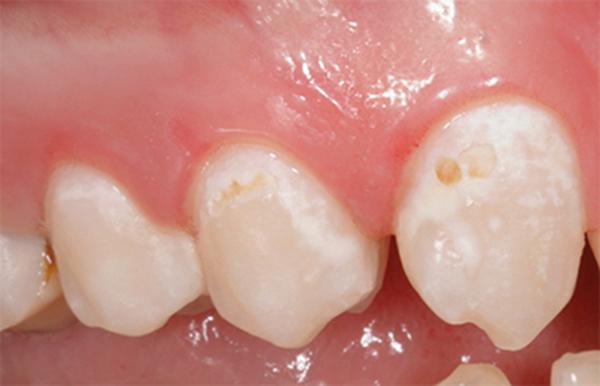

Бесконтактную терапию применяют на начальной стадии заболевания, когда кариес выражен лишь в виде небольших меловых или коричневых пятен. Данные методы отличаются своей быстротой и безболезненностью. Ещё один важное преимущество — врачу не нужно удалять ткани зуба.

Реминерализация применяется при появлении на эмали пятен.

В результате развития кариозного процесса меняется состав эмали, минералов становится значительно меньше, ослабевают её защитные функции, что приводит к пигментации.